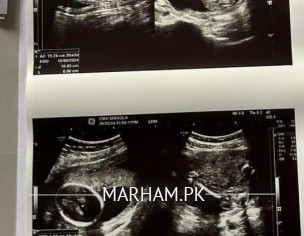

we have this 19 week scan and want to find out if its a girl or boy?

mam can you comment if its girl or boy from scan?

no pic of gender

mam check

mam this is picture of gender

this is head